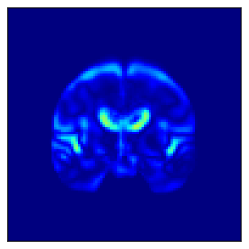

Fig. 5 shows the difference in the reconstructed images (the coronal, sagittal, transverse planes) with and without perturbation to one dimension of the low-dimensional representations that most affect the disease features between AD and CN. This one dimension is chosen to have the largest expected value of the difference in the mean vector ( dim) between AD and CN.

In Fig. 5, the influence of dimensions that may contribute to the diagnosis of AD is examined, and it can be seen that the naïve -VAE captures not only the important areas around the ventricles shown in Fig. 2 but also the edges of the brain and other areas. Loc-VAE, however, is more limited and captures this region better. This result shows that Loc-VAE acquires a specific dimension of the disease features on low-dimensional representation. Disease feature–specific dimensions serve as materials for the neurologist to assess similar cases displayed by CBIR.